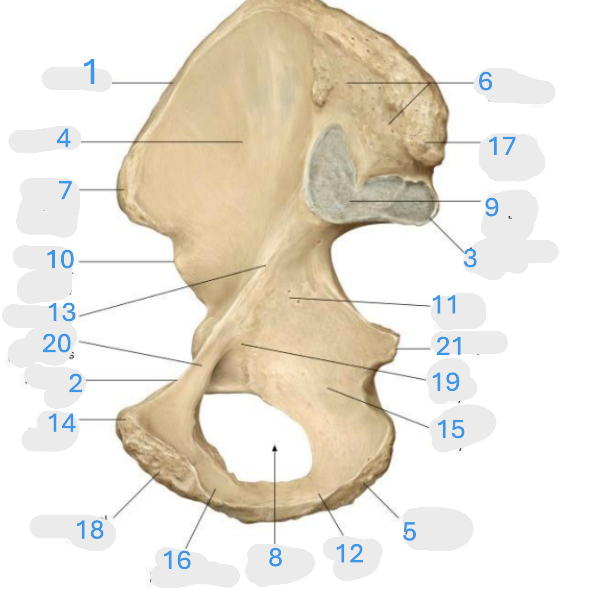

Where is the iliac crest

1

Where is the pectineal line

2

Where is the posterior iliac spine

3

Where is the iliac fossa

4

Where is the ischial tuberosity

5

Where is the iliac tuberosity

6

Where is the anterior superior iliac spine

7

Where is the obturator foramen

8

Where is the auricular surface of the ilium

9

Where is the anterior inferior iliac spine

10

Where is the ilium body

11

Where is the ischial ramus

12

Where is the arcuate line

13

Where is the pubic tubercle

14

Where is the ischium body

15

Where is the inferior pubic ramus

16

Posterior superior iliac spine

17

Where is the symphyseal surface

18

Where is the pubis body

19

Where is the superior pubic ramus

20

Where is the ischium body

21